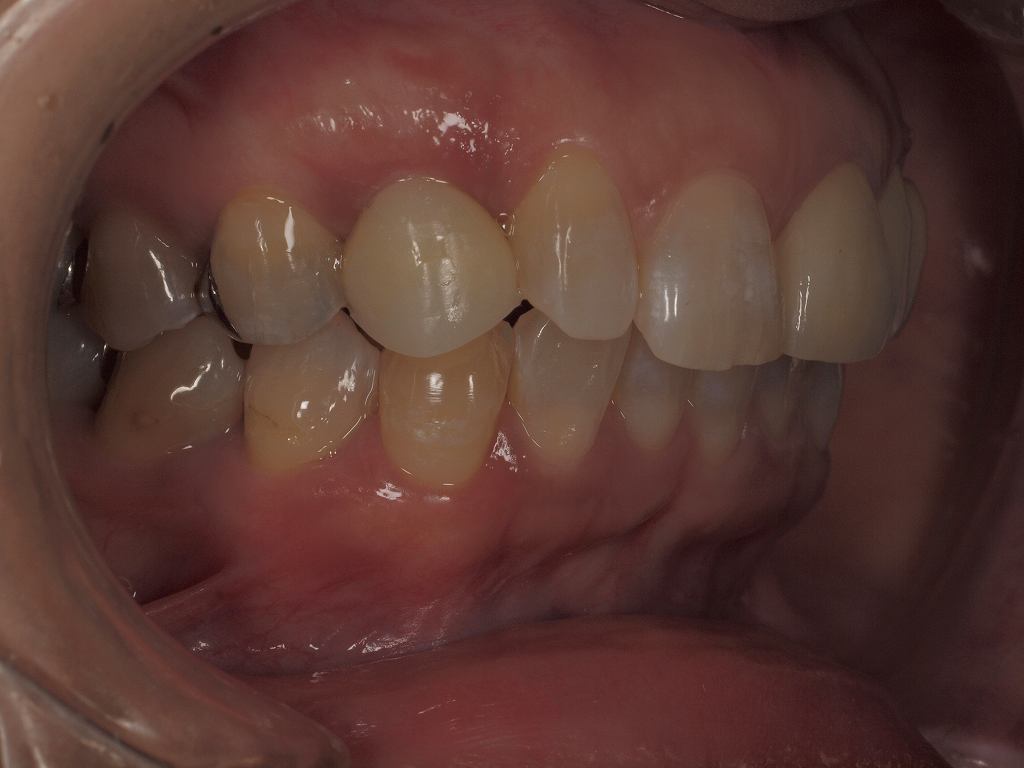

仮歯からプロビジョナルを入れていったところになります

印象時になります

歯肉形態も仕上がっています